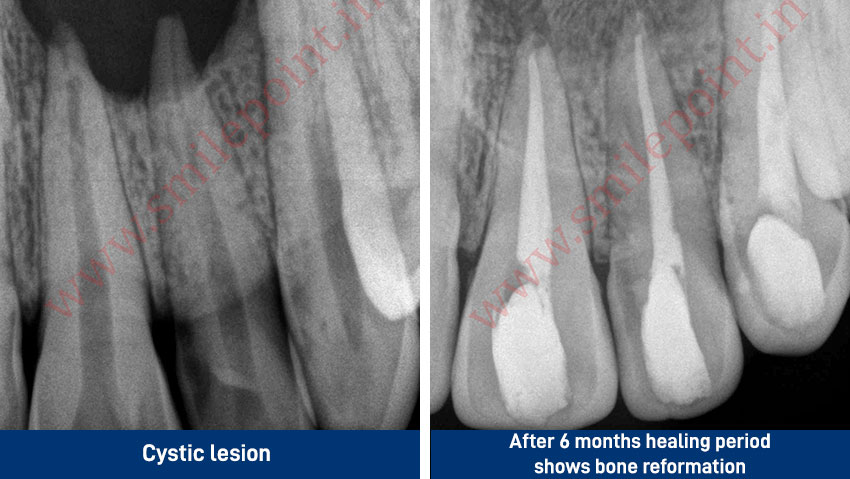

Computer assisted and navigated root canal treatment